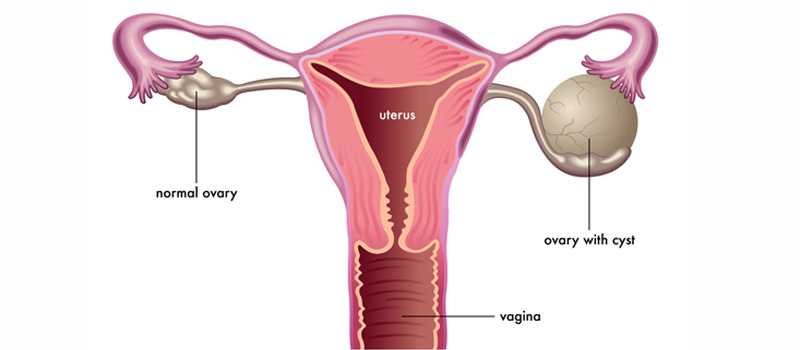

• The ovaries are part of the female reproductive system. They’re located in the lower abdomen on both sides of the uterus. Women have two ovaries that produce eggs as well as the hormones estrogen and progesterone.

• An ovarian cyst is a larger fluid-filled sac (more than 3 cm in diameter) that develops on or in an ovary. A cyst can vary in size from a few centimetres to the size of a large melon. Many women will develop at least one cyst during their lifetime. In most cases, cysts are painless and cause no symptoms

• Ovarian cysts may be thin-walled and only contain fluid (known as a simple cyst) or they may be more complex, containing thick fluid, blood or solid areas.

• An ovarian cyst is a fluid-filled sac that develops on a woman's ovary. They're very common and don't usually cause any symptoms.

• Most ovarian cysts occur naturally and disappear in a few months without needing any treatment.

• The ovaries

• The ovaries are two small, bean-shaped organs that are part of the female reproductive system. A woman has two ovaries – one each side of the womb (uterus).

• The ovaries have two main functions:

• to release an egg approximately every 28 days as part of the menstrual cycle

• to release the female sex hormones, oestrogen and progesterone, which play an important role in female reproduction

• Ovarian cysts may affect both ovaries at the same time, or they may only affect one.

There are various types of ovarian cysts, such as dermoid cysts and endometrioma cysts. However, functional cysts are the most common type. The two types of functional cysts include follicle and corpus luteum cysts.

• Follicle cyst

During a woman’s menstrual cycle, an egg grows in a sac called a follicle. This sac is located inside the ovaries. In most cases, this follicle or sac breaks open and releases an egg. But if the follicle doesn’t break open, the fluid inside the follicle can form a cyst on the ovary.

• Corpus luteum cysts

Follicle sacs typically dissolve after releasing an egg. But if the sac doesn’t dissolve and the opening of the follicle seals, additional fluid can develop inside the sac, and this accumulation of fluid causes a corpus luteum cyst.

• Some women develop a condition called polycystic ovary syndrome. This condition means the ovaries contain a large number of small cysts. It can cause the ovaries to enlarge. If left untreated, polycystic ovaries can cause infertility.